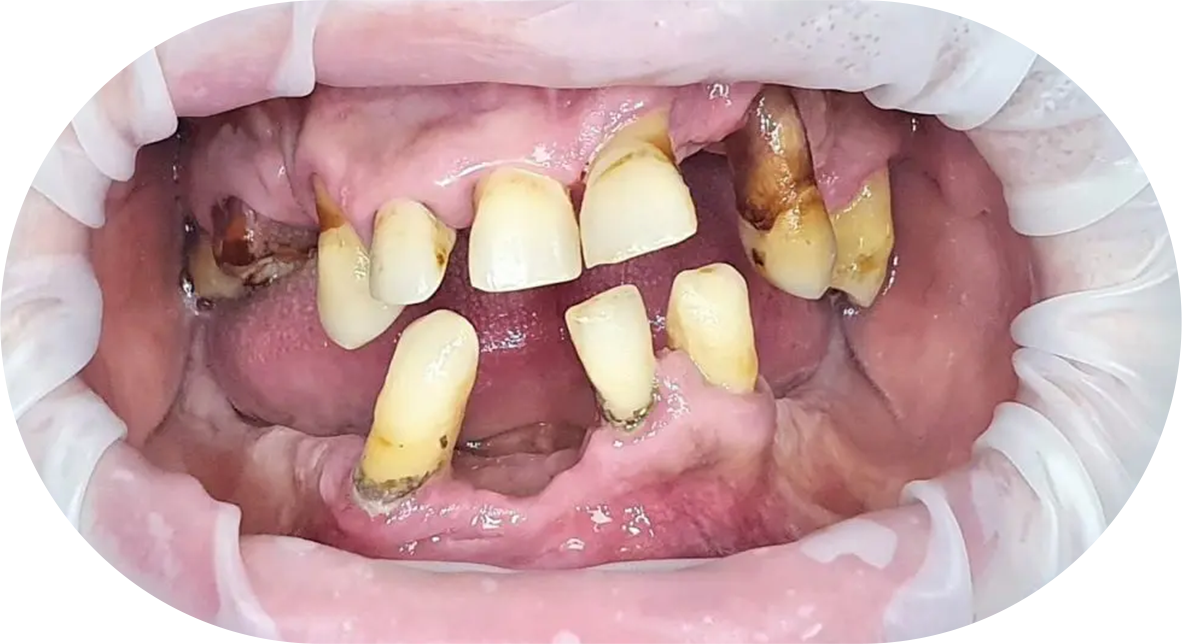

Te afli în una din situații?

- Suferi de o boală paradontală?

- Ai carii severe care distrug dantura?

Intervenția chirurgicală explicată